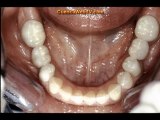

Dr Fabian Polo Barzallo es un experto en ortodoncia en Cuenca, Ecuador. Direccion de la clinica: Av Paucarbamba 5-124 y Tomillos, Cuenca, Ecuador. Tel: (+593)7-409-68-39, Email: fapo5@hotmail.com . Distributed by Tubemogul.